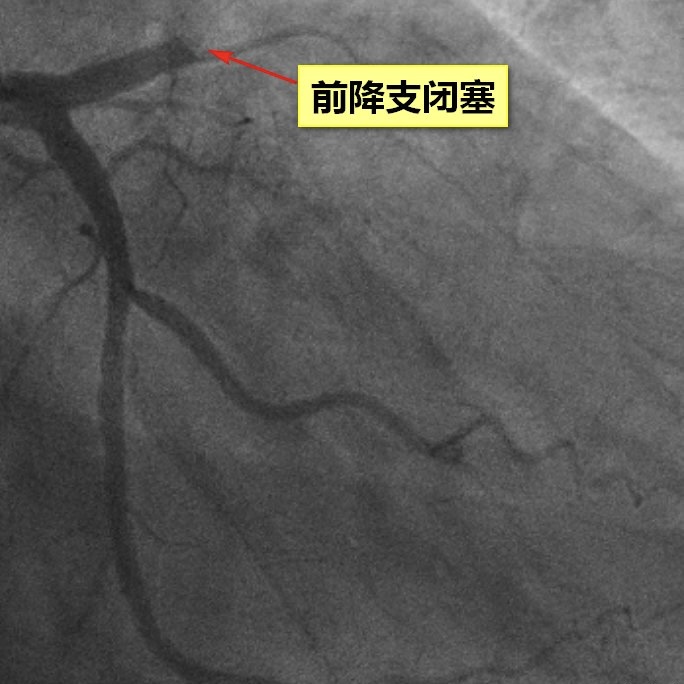

在医护团队高效协作下,患者被迅速转送至导管室,为抢救争取了宝贵时间。胸痛中心多科室高效联动,急诊介入手术迅速开展。从患者进入急诊科至导丝通过闭塞血管(前降支),仅用时40分钟,远低于国家胸痛中心90分钟的标准,实现了迅速血运重建,最大程度挽救了濒危心肌。这一过程充分体现了“时间就是心肌,时间就是生命”的急救理念,也彰显了医院胸痛中心在急危重症心血管疾病救治中的专业能力和协同效率。